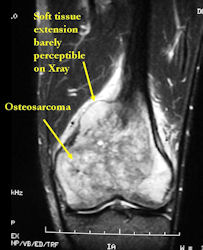

- Most conventional osteosarcomas (90-95%) extend through the bone into the soft tissues and form a soft tissue mass outside of the bone

MRI with contrast (gadolinium) of the extremity Best for:

- determining intraosseous extent (size) of the tumor and size of the soft tissue component

- detecting subtle tumor calcification and ossification diagnostic of an osteosarcoma

- evaluating cortical bone integrity and penetration beyond the cortex